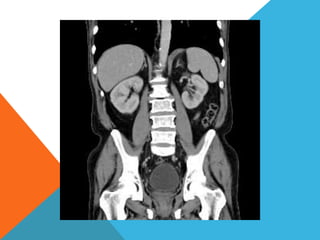

El paciente presentó síntomas de sangrado digestivo y pérdida de peso. Exámenes revelaron gastritis crónica asociada a H. pylori. Un tumor fue descubierto en una colonoscopia normal. La cirugía removió un tumor fibroide solitario, una rara neoplasia mesenquimal que usualmente crece lento y tiene bajo potencial de malignidad. El pronóstico después de la remoción quirúrgica es generalmente bueno.